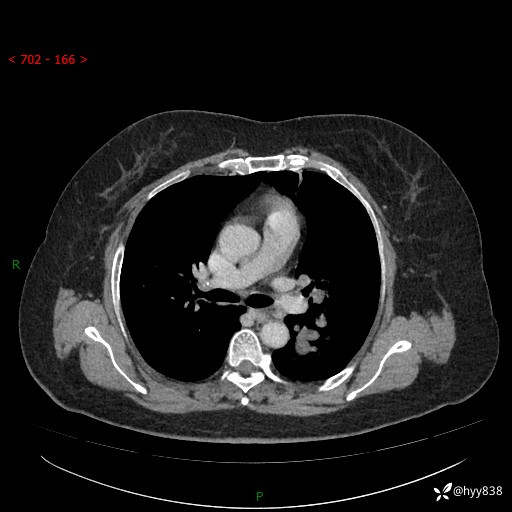

简要病史:患者于8年前体检行胸部CT检查发现左上肺结节(4mm),患者平素间断咳嗽咳痰,无心慌、胸闷、胸痛、呼吸困难、低热、盗汗,无头痛、头晕,无腹痛、腹胀等不适,未行特殊处理,定期复查。2023-09-21胸部CT示左上肺结节(2cm)较前增大,2024-02-01胸部CT示左上肺尖后段(39*32mm),左侧肺门及纵隔淋巴结增大,现患者欲求手术治疗,遂来我院就诊,以“左上肺结节”收入我科。 患者自起病以来,精神可,睡眠可,饮食可,大小便正常,体重无明显改变。

辅助检查:CT

胸部CT平扫

增强(动脉期+静脉期)